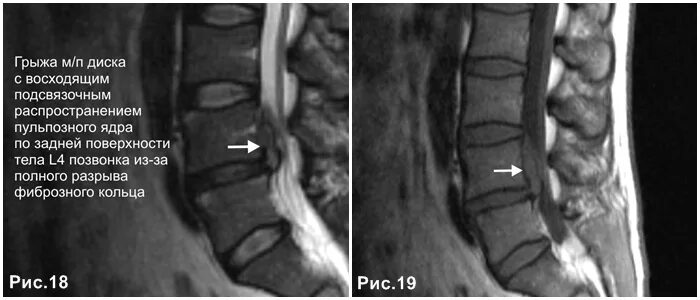

Каудальная миграция грыжи диска